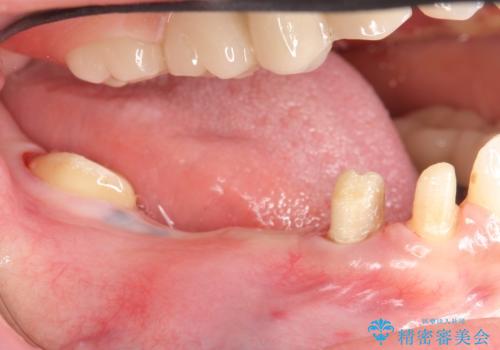

その後右下5、6番目にはインプラントを埋入し、右下3、4、5、6、7番の歯の補綴をオールセラミッククラウンによって行いました。

今回用いたオールセラミッククラウンはジルコニアフレームという白い素材の上にセラミックを盛っているため、審美性が非常に高いのが特徴です。

また、ジルコニアは人工ダイヤモンドの材料にも使われているほど高い強度を持っており、そのためオールセラミッククラウンは審美性だけでなく、奥歯やブリッジの補綴も可能とするクラウンです。